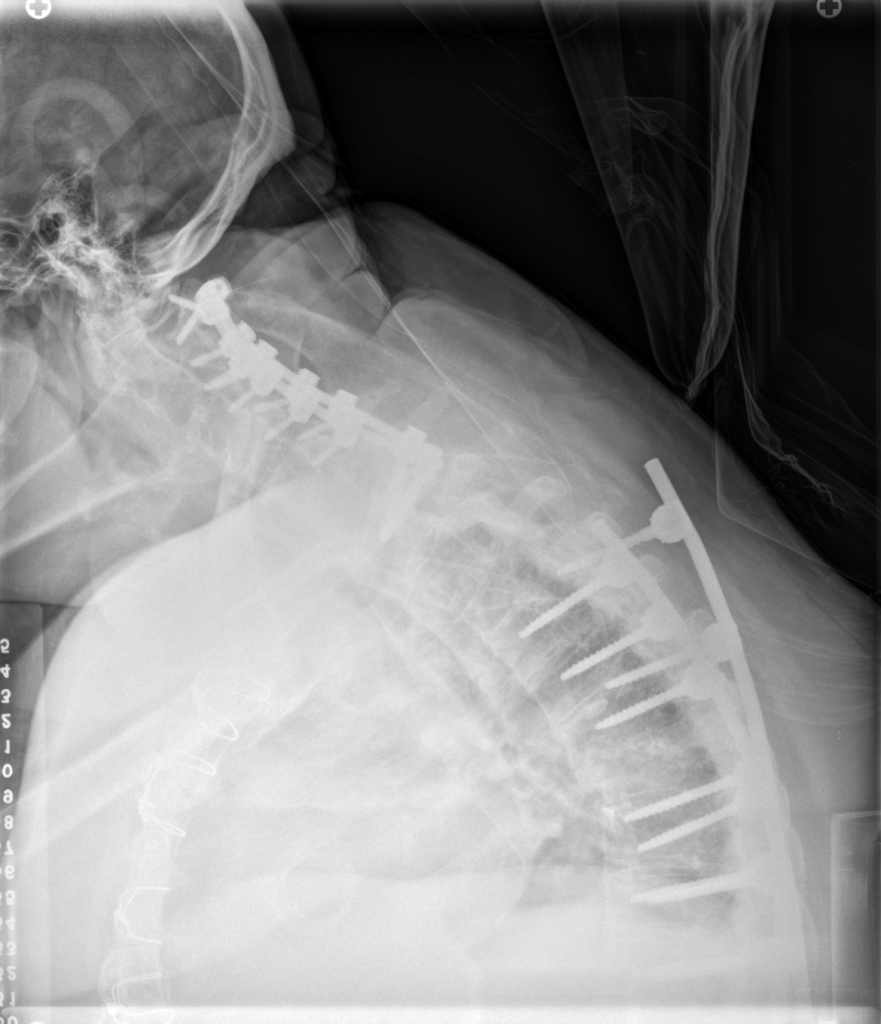

When I met Dr. Kim, he explained everything in terms I could understand, gave me time to process, and answered all my questions. I continued seeing him as a DISH patient until February 2023, when I suffered a thoracic fracture, followed by a cervical fracture in July 2023. Both required emergency surgeries, and after discharge, I was left with cervical kyphosis and displaced hardware.

The cervical fracture caused a spinal cord injury, leaving me paralyzed in both arms for 12–18 months. My rehabilitation journey included intensive inpatient therapy, subacute rehab, home therapy, and finally outpatient therapy. Once I felt ready to discuss another spinal surgery, I returned to Dr. Kim.

After reviewing my x-rays, CT, and MRI, Dr. Kim recommended a Pedicle Subtraction Osteotomy (PSO). During surgical clearance, an abnormal EKG required cardiac evaluation. I had a congenital heart defect repaired in 2014 with valve replacement, and my cardiology team determined the valve needed repair before spinal surgery. This caused significant delays, as insurance denied authorization three times before approving a valve-in-valve repair in November 2024.

Finally, I was cleared for the PSO with Dr. Kim. Throughout this entire process, Dr. Kim and his team were incredible - supportive, patient, and reassuring. Today, my posture has improved significantly, and I can hold my head high, smile, and be thankful for the outstanding care I received.